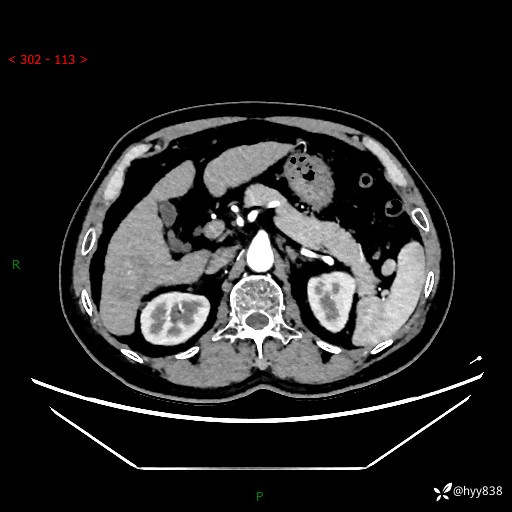

增强动脉期